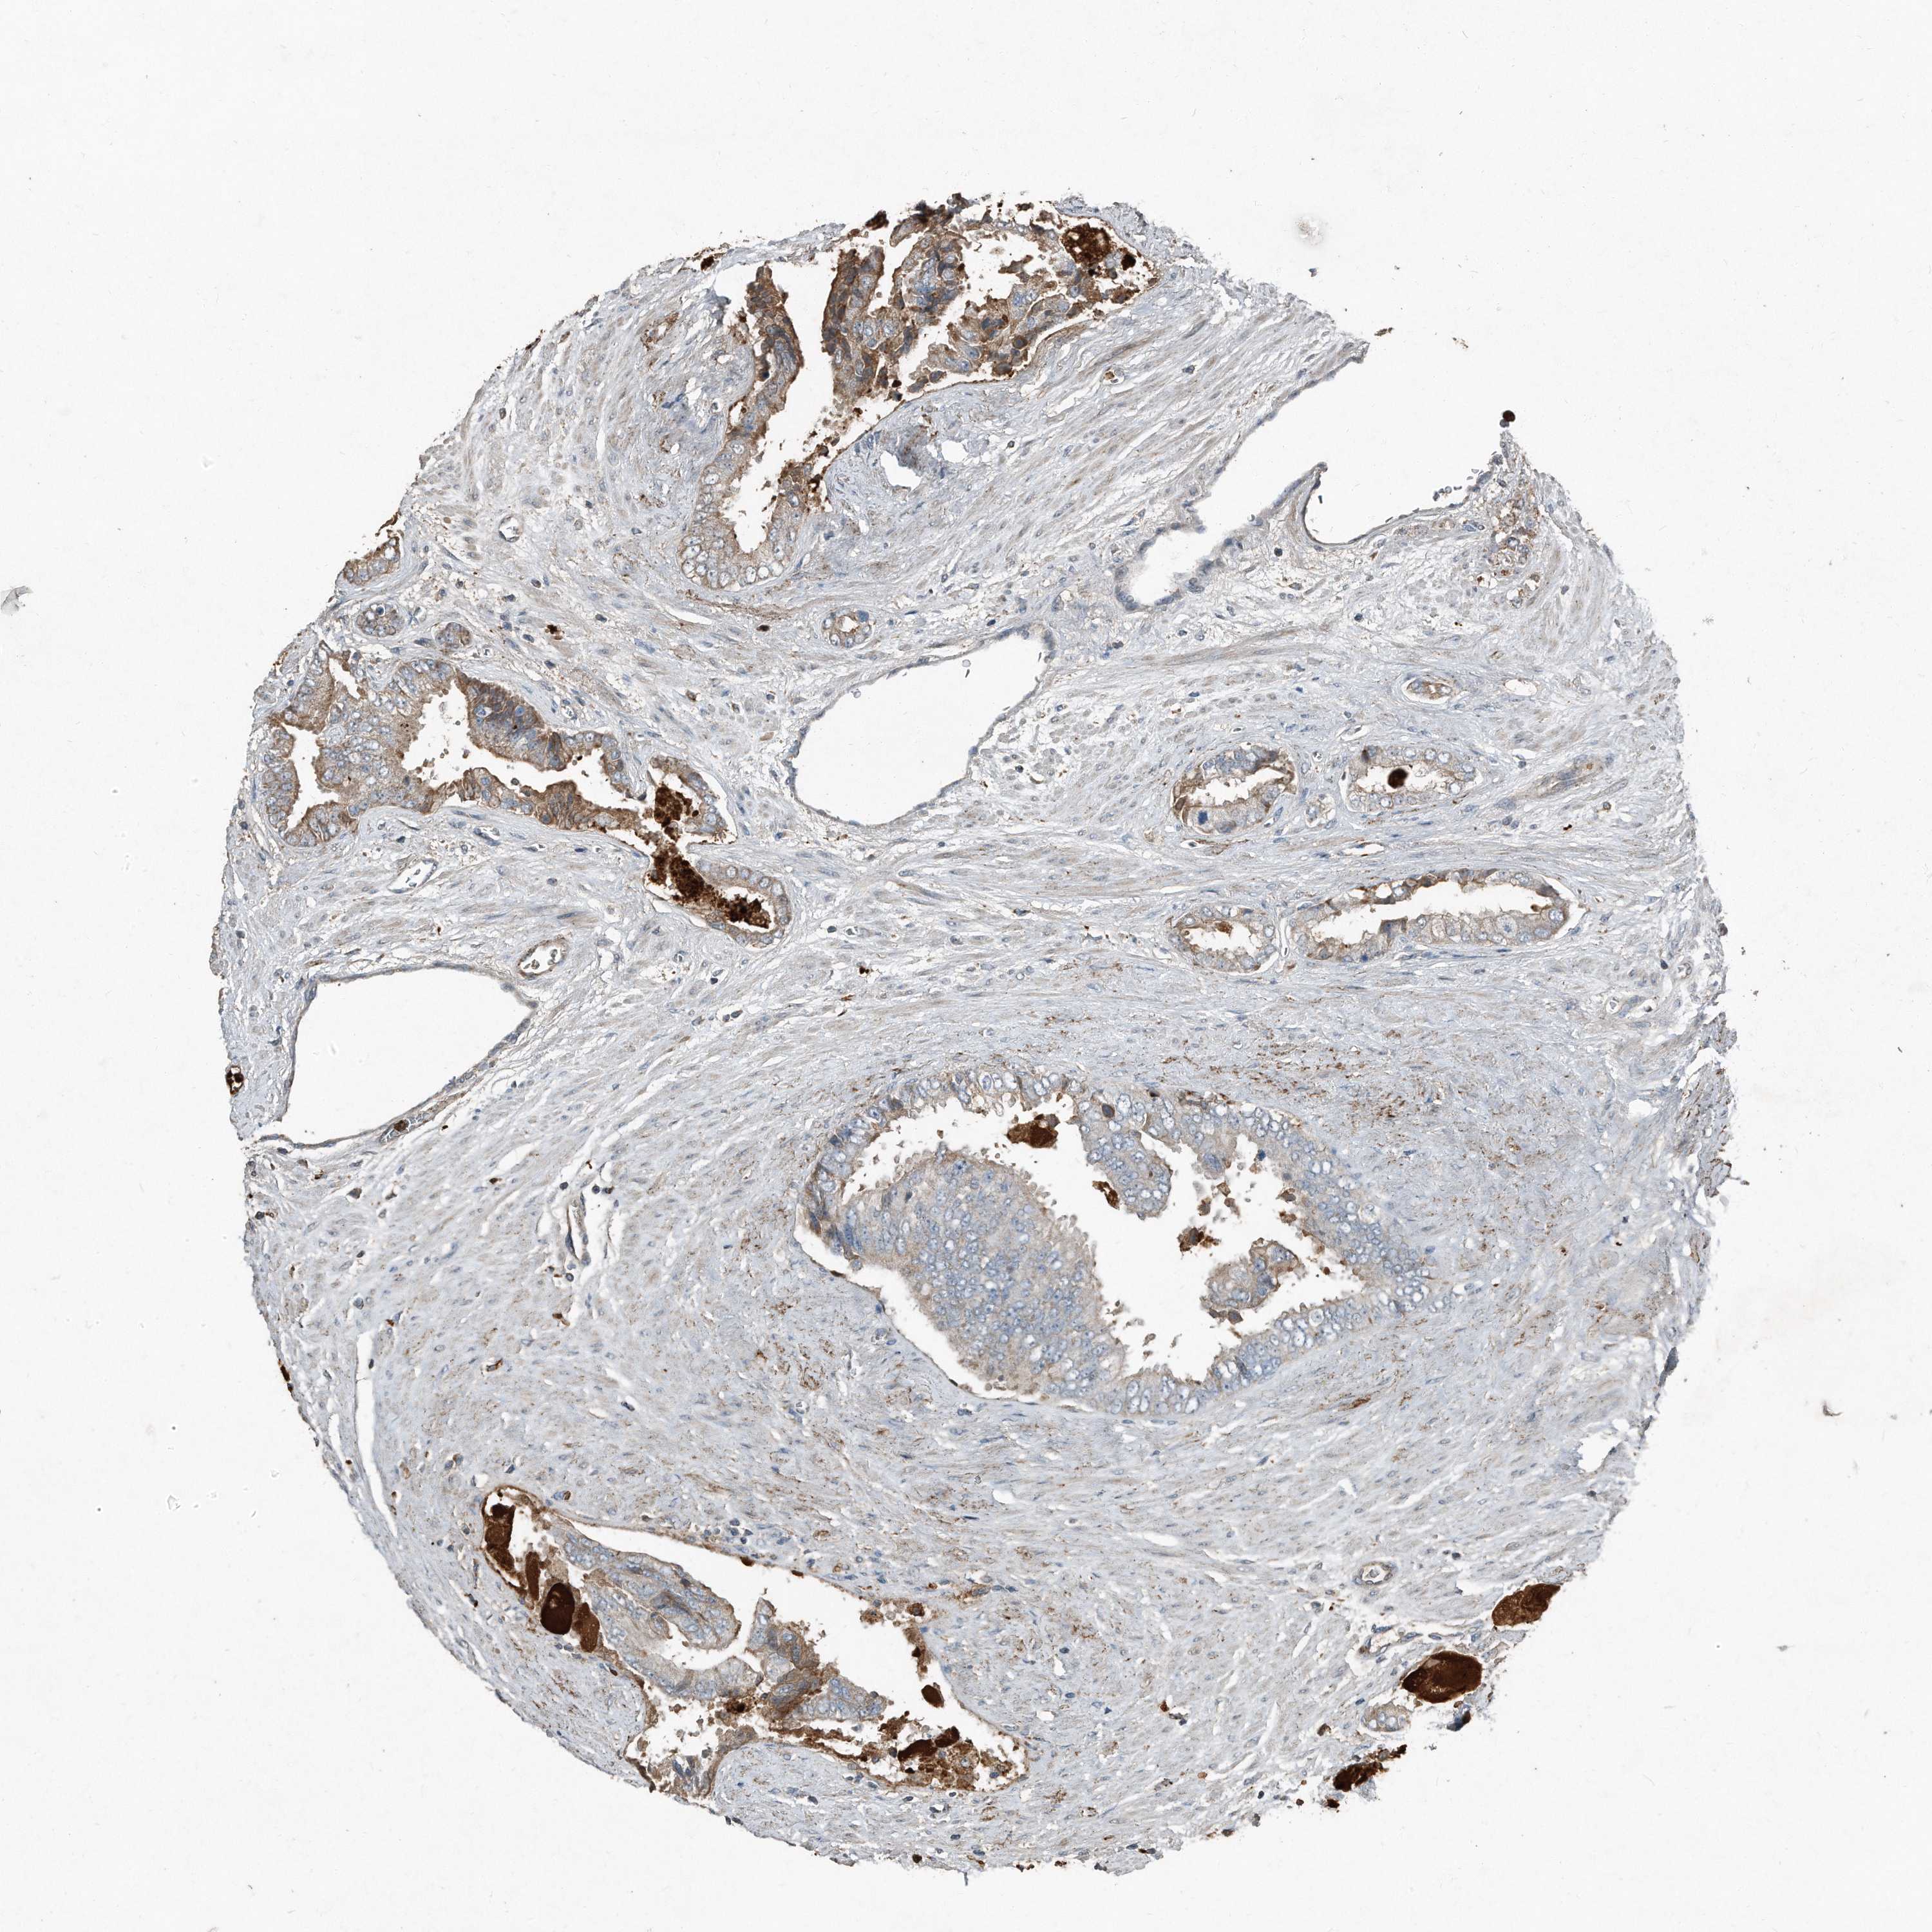

PROSTATE CANCER - Protein expressioni

A mouse-over function shows sample information and annotation data. Click on an image to view it in a full screen mode. Samples can be filtered based on level of antibody staining by selecting one or several of the following categories: high, medium, low and not detected. The assay and annotation is described here.

Note that samples used for immunohistochemistry by the Human Protein Atlas do not correspond to samples in the TCGA dataset.

Antibody stainingi

Antibody staining in the annotated cell types in the current human tissue is reported as not detected, low, medium, or high, based on conventional immunohistochemistry profiling in selected tissues. This score is based on the combination of the staining intensity and fraction of stained cells.

Each image is clickable and will lead to virtual microscopy that enables deeper exploration of all samples and also displays staining intensity scores, fraction scores and subcellular localization as well as patient and tissue information for each sample.

Antibody HPA029577

Antibody CAB002151

Adenocarcinoma, High grade

Adenocarcinoma, Low grade

Adenocarcinoma, Medium grade